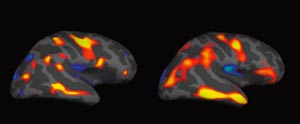

Utgangspunktet var at den affiserte hjerneutvikling som kan ses hos premature, kan ha negative følger for barnets senere utvikling. I studien ble MR gjennomført ved hjelp av en ny automatisert teknikk, etterfulgt av morfometriske analyser. Metoden omfatter målinger av hjernebarkens tykkelse, areal og volum for hvert enkelt individ og sammenlikner hjernens anatomi på tvers av gruppene.

Det ble påvist strukturelle forskjeller mellom prematurgruppen og de andre mht. kortikal overflate, areal og volum og forskjellene var størst for de minste og mest premature. Blant premature var det en sammenheng mellom både overflateareal og kortikalt volum og målt IQ. Mengden grå substans i forhold til hjernens totale volum var lavere hos de premature sammenliknet med kontrollpersonene.

Forfatterne mener at den nye MR-metoden gjør det mulig å studere sammenhenger mellom anatomiske hjerneforandringer og kognitive, sosiale og atferdsmessige avvik og psykisk sykdom som er observert hos barn og unge som var født prematurt.